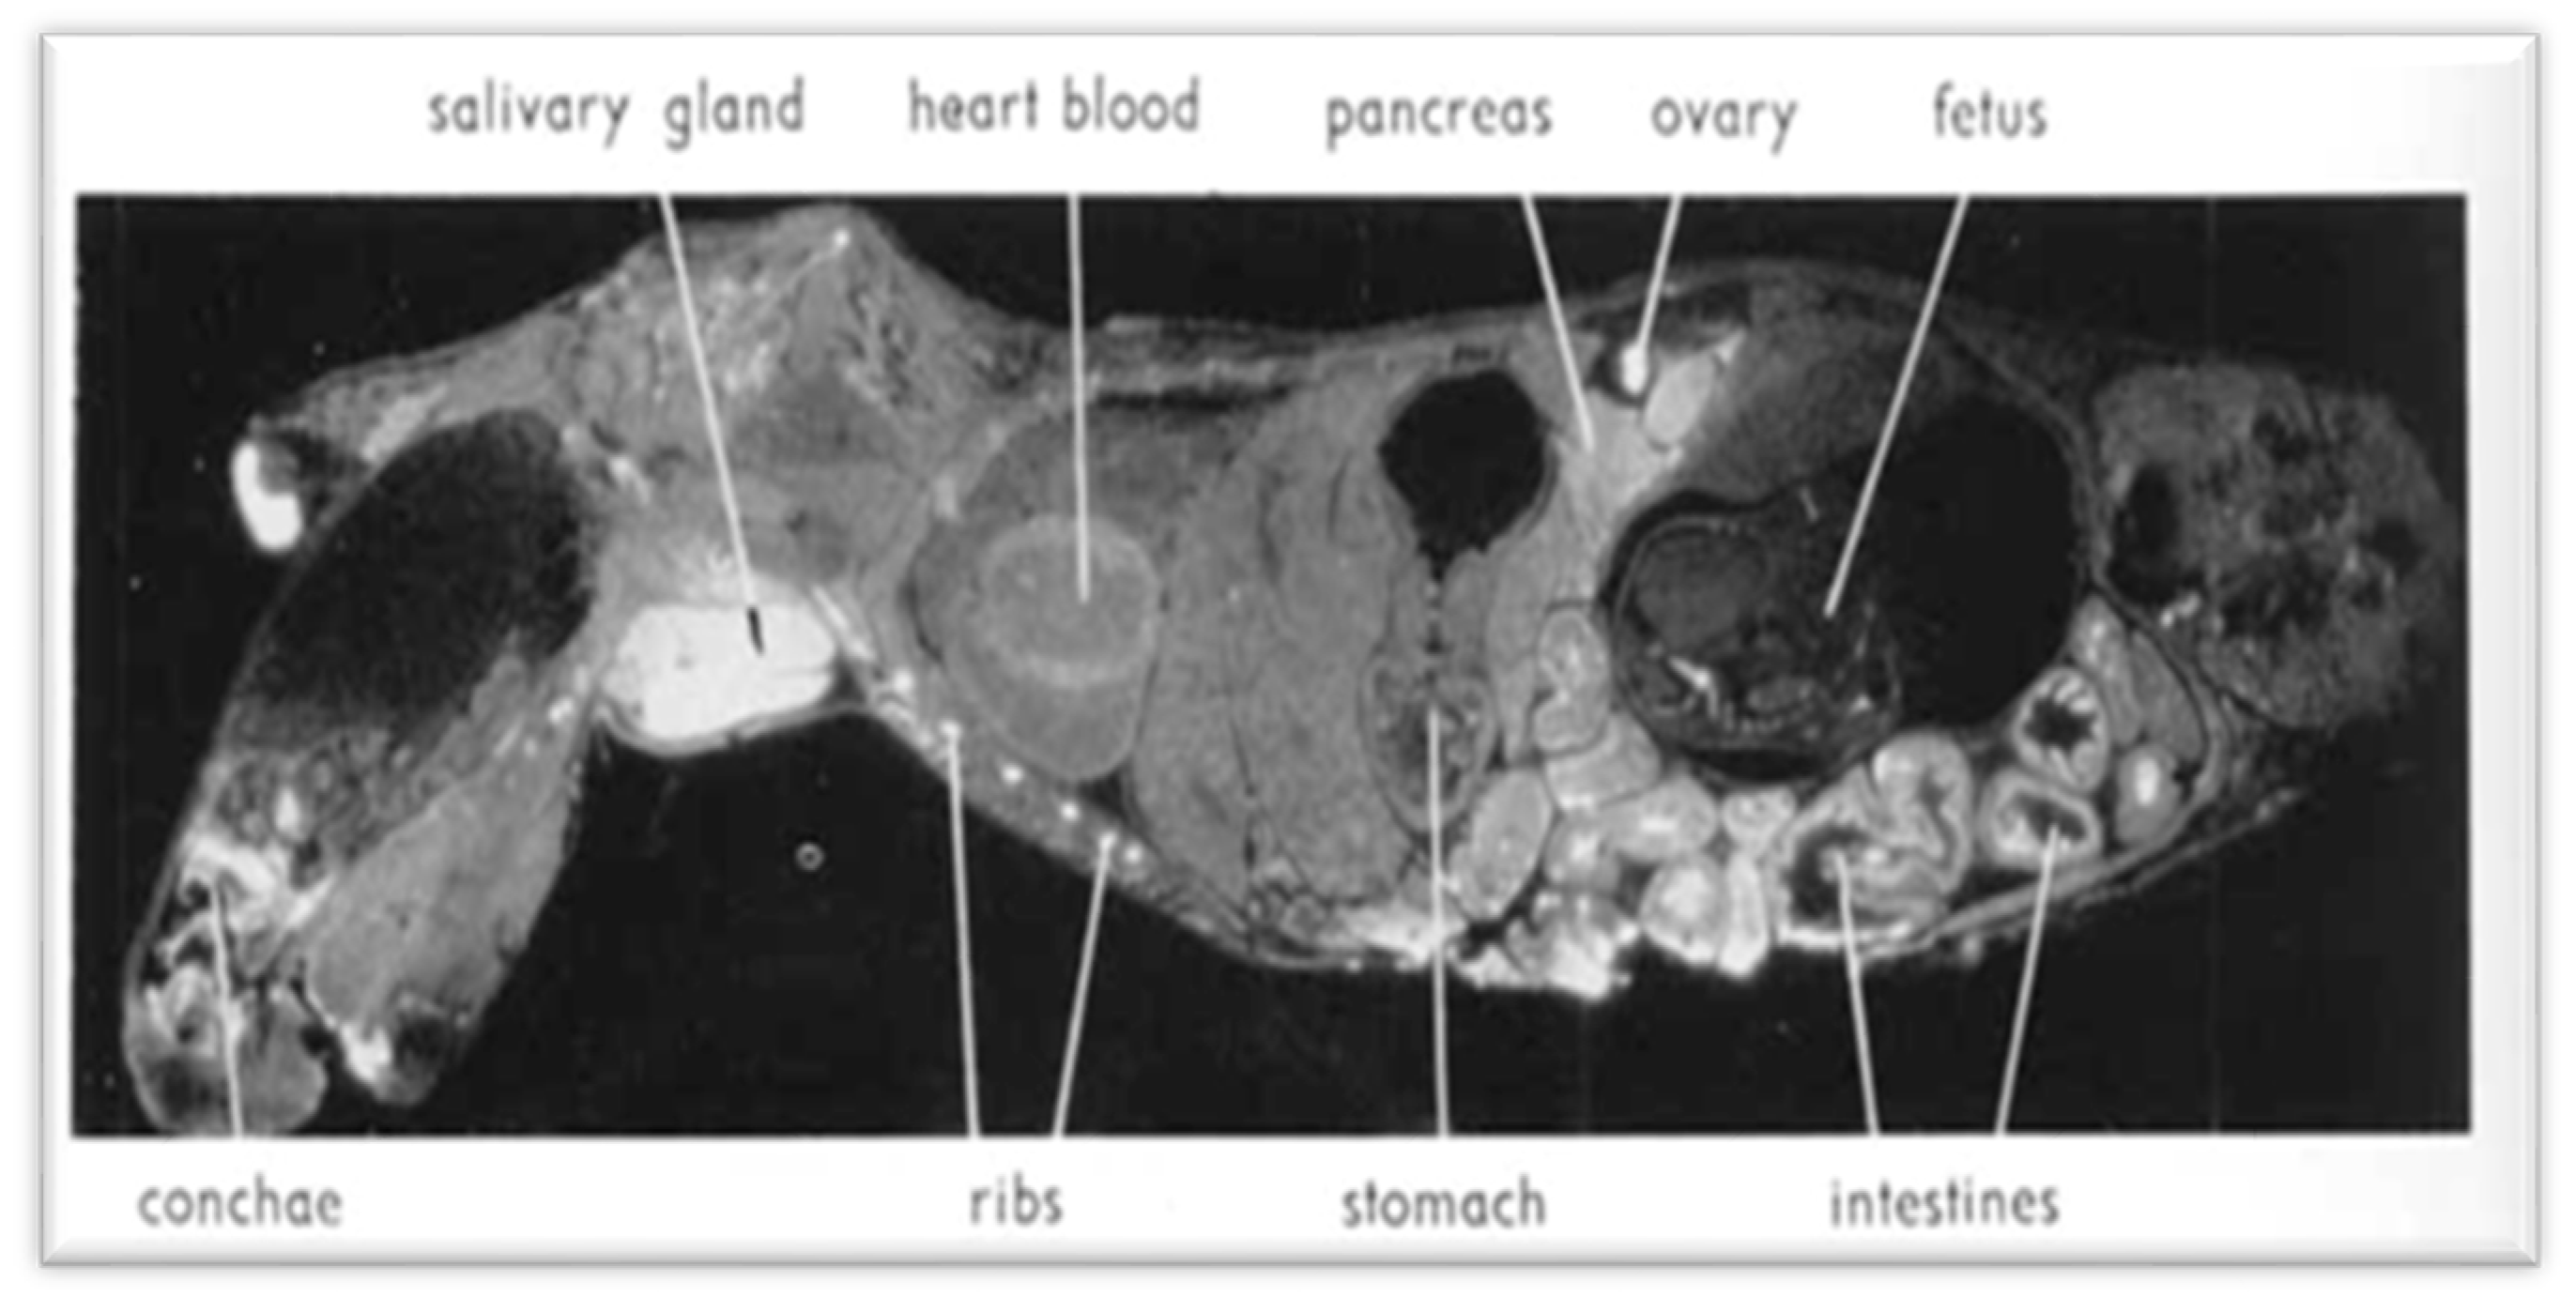

Upon renal insufficiency in man and rat, cesium level increases by 100% in the pancreatic tissue [32]. Nelson et al. [13] showed that 137-Cs is concentrated in larger quantity in pancreatic exocrine cells, where most PCs (about 90%) originate, and showed a non-homogeneous selectivity for Cs in different organs: lower in the liver and fetuses (Figure 4 and Figure 5). This was also reported in the autopsy of the liver by Bandazhevsky [33].

Figure 4.

Autoradiograms showing the distribution of 137-Cs in a pregnant mouse 5 min after intravenous injection. White areas correspond to high radioactivity. High uptake in cartilaginous parts of ribs and vertebrae and in salivary gland and intestine. The pancreas shows the same high level of activity as the intestinal mucosa. (Reproduced from Nelson et al. [13] with permission of Acta Radiologica, 1961).

Figure 5.

Autoradiogram showing 137-Cs distribution in a pregnant mouse 6 h after intravenous injection. White areas correspond to high radioactivity. Uptake is high in the salivary gland, pancreas, and intestine. In fetuses, concentration is significantly lower than in the mother. In the pancreas, the islets of Langerhans appear to have a slightly lower activity than the acinar tissue. (Reproduced from Nelson et al. [13] with permission of Acta Radiologica, 1961).

The high concentration of 137-Cs in the germinal cells of the ovary and the testicle explains the genetic and reproductive damage, sterility, azoospermia, and furthermore, children’s heart diseases and malformations in the population, and also genetic mutations in animals and plants after the Chernobyl accident [13,33]. In the Gomel region, which has been heavily contaminated by the radioactive fallout of the Chernobyl disaster, the damage has also been studied in the rural population since 1990. Children have shown absorption of radiocesium and other radionuclides more than double that of adults. In autopsies of contaminated children, Bandazhevsky found a high accumulation of 137-Cs in the pancreas (and also in thyroid and adrenal glands) detecting levels up to 40–45 times higher than in the liver [33].